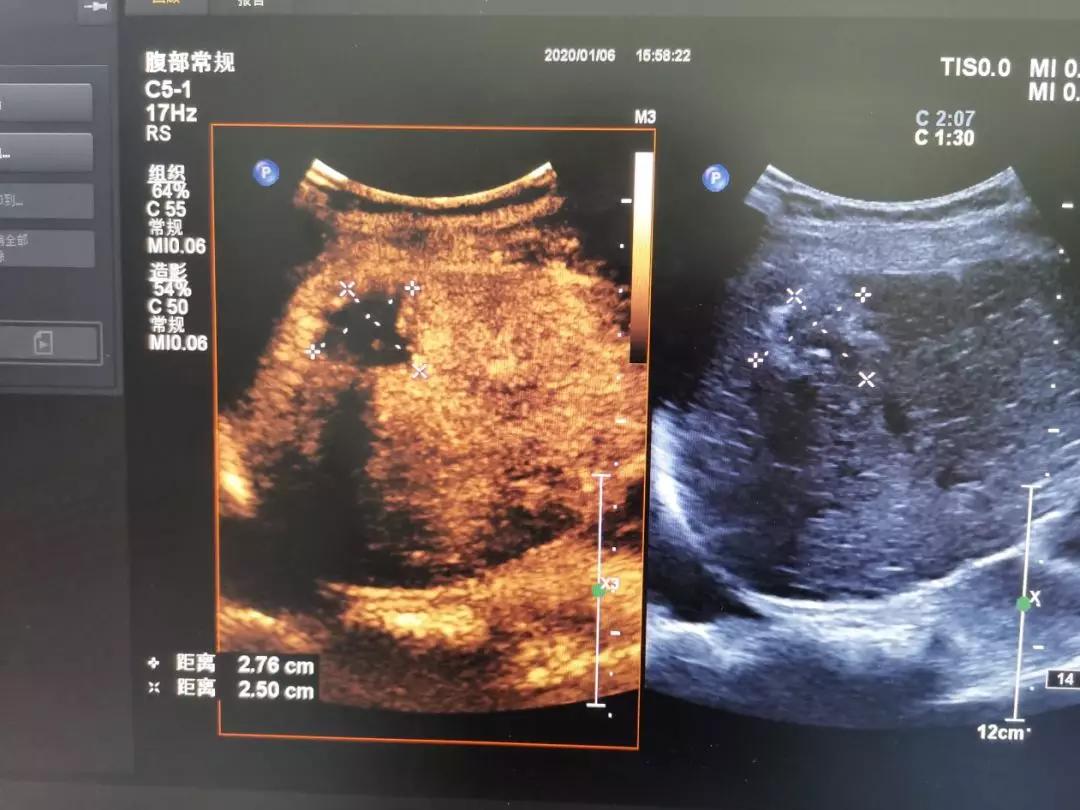

邻近肝包膜下的肝癌病灶,射频消融术后造影,病灶无增强

邻近胃肠的肝癌病灶,术前造影呈明显增强

超声造影是介入超声的一个好帮手,在整个手术的术前、术中、术后都需要用到超声造影。术前,主要是用来做评估是否需要做射频消融术及其范围。术中,超声造影可以引导射频消融术的位置。术后,主要是用于评估射频消融术的效果。多种超声技术的联合应用,可为肝癌精准的术前诊断、术中定位、术后评估起到重要作用。